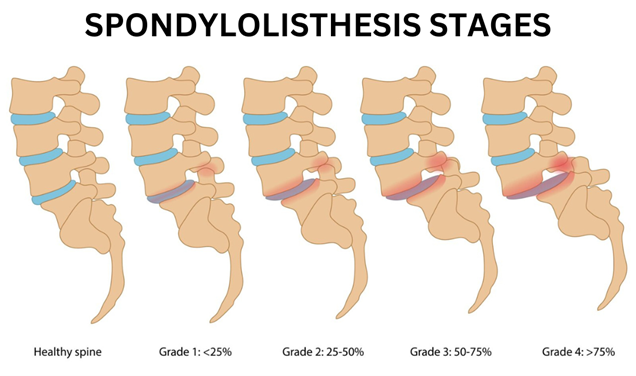

A special X-ray called dynamic x-ray of Lumbar spine reveals instability of the spine. Based on the X-Ray, grade of slip is evaluated.

No, all Spondylolisthesis don’t need surgery. Surgery is required or not, depends on whether the listhesis is stable or unstable, the grade of listhesis and the presence of nerve symptoms. Grade 1 stable Spondylolisthesis with only mild back pain and no neurological symptoms can be managed with physiotherapy and medications.